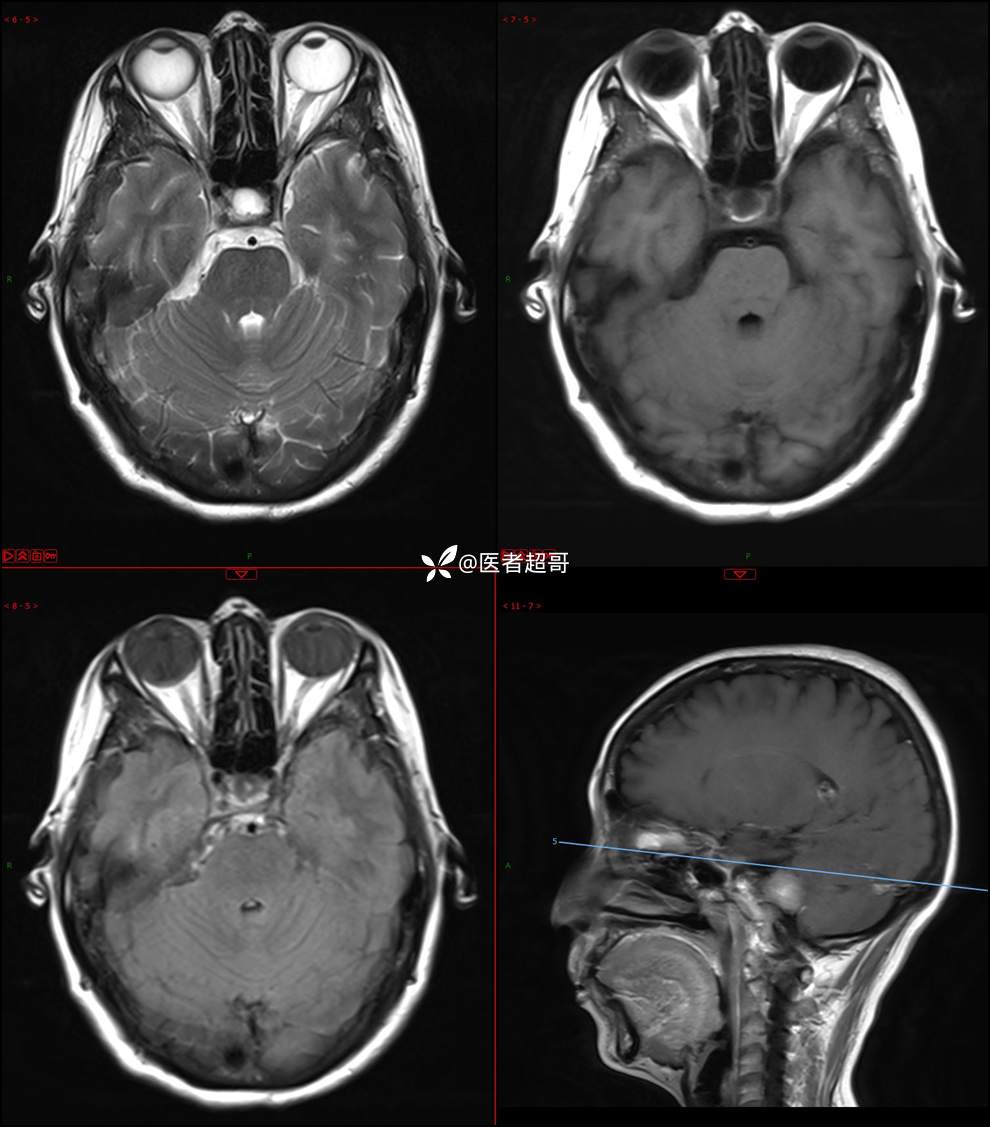

CPA区占位,是鞘瘤?脑膜瘤?请赏析!

主 诉:耳鸣3年,头晕伴恶心4天。

现病史:患者3年前出现耳鸣,蝉鸣音,反复发作,夜间自觉明显,于2018年8月至我院耳鼻喉科就诊,行颅脑CT检查未发现明显异常改变,给予对症处理(具体不详);4天前突发头晕,伴明显恶心,至市人民医院就诊,行颅脑CT未见明显异常,颅脑MRI发现右侧桥脑小脑角区占位性病变。本次发病来无明显头痛,无肢体抽动,无大小便失禁。为求进一步诊治,遂来我院门诊,以“听神经良性肿瘤”收住入院。发病来,患者神志清,精神可,二便正常,饮食可,睡眠不佳,近期体重无明显变化,否认癫痫发作病史。